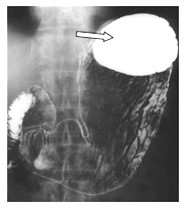

Przedstawiony obraz radiologiczny został zarejestrowany podczas badania jelita

Ilustracja do pytania 23

A. cienkiego po doustnym podaniu środka kontrastującego.

B. cienkiego po doodbytniczym podaniu środka kontrastującego.

C. grubego po doustnym podaniu środka kontrastującego.

D. grubego po doodbytniczym podaniu środka kontrastującego.